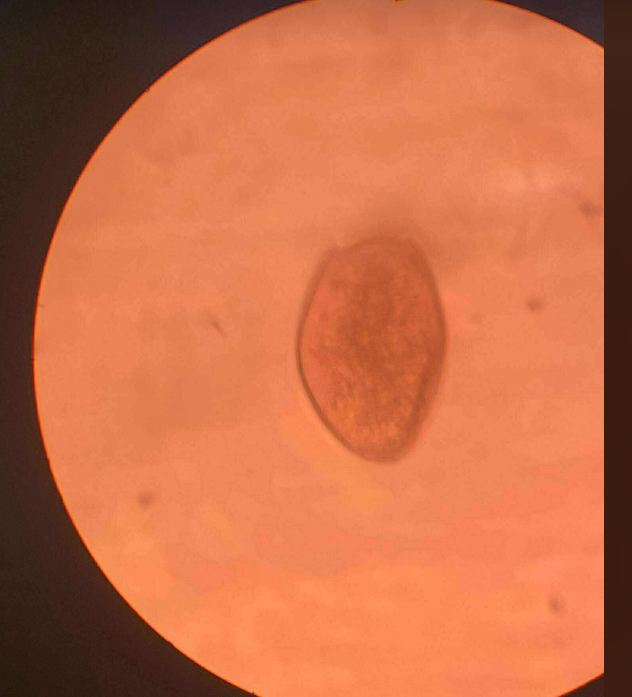

DIPYLIDIUM CANINUM OVA